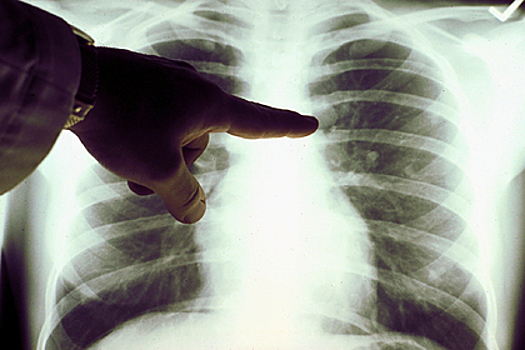

Женщина обратилась за медицинской помощью, но опухоль была так мала, что врачи сначала не смогли найти ее. Позже они обнаружили новообразование диаметром шесть миллиметров. Как оказалось, у Отуэй была вторая стадия онкологического заболевания. Опухоль удалили, химиотерапия пациентке не потребовалась.